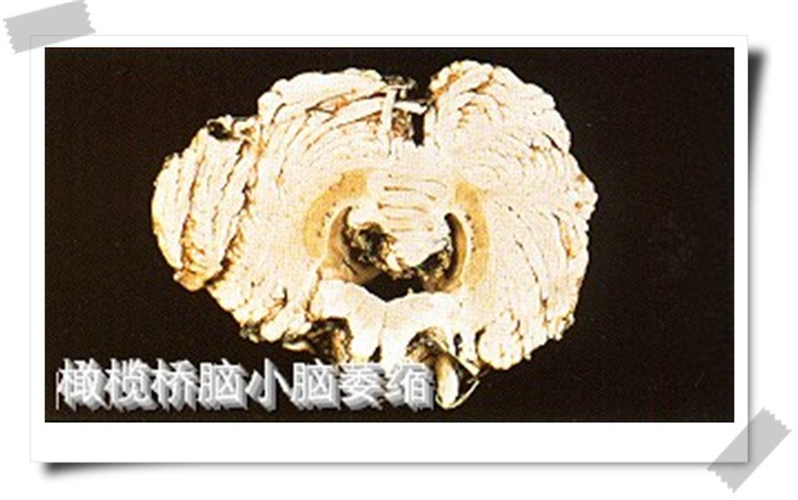

橄欖橋腦小腦腦萎縮標本

橄欖橋腦小腦腦萎縮